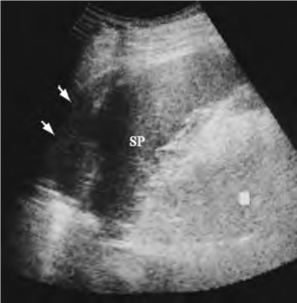

图24-6 外伤后脾破裂(包膜下血肿)声像图

脾大,箭头所示为包膜下血肿。SP:脾脏